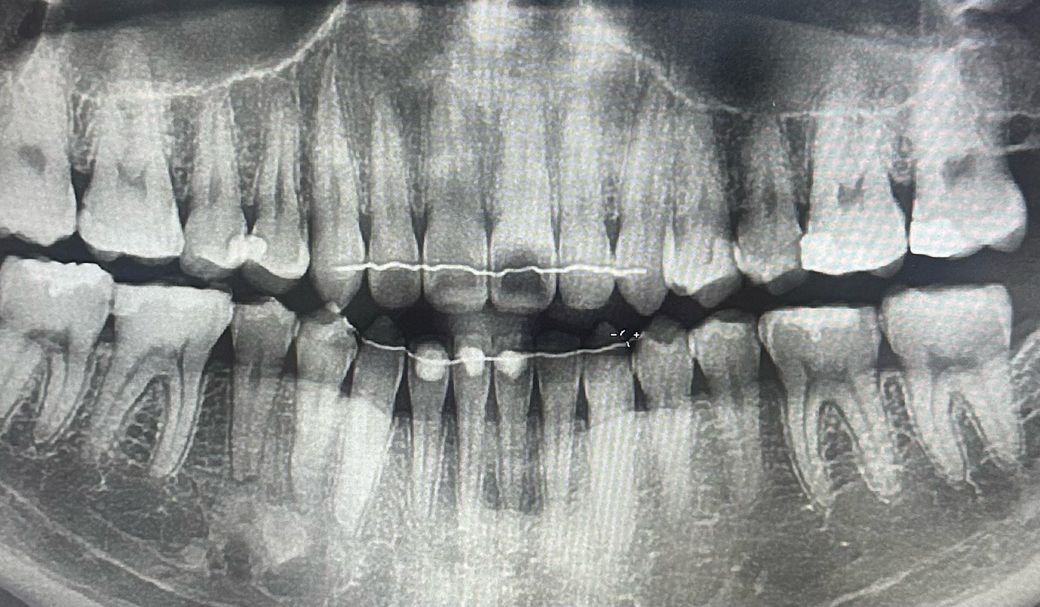

치아 신경 손상??이라는 진단을 받았는데 맞을까요?

치아가 가만히 있을때는 안아프고, 뭐 먹거나 씹으면 통증이 있습니다. 신경치료를 하라고 말을 하던데 가만히 있을때는 아프지 않은데 신경치료를 하야할까요?

• 1번 째 사진

사진으로만 봤을 경우에는 큰 충치가 보이진 않습니다. 하지만 치아에 금이가 있거나 했다면 해당 부위가 음식을 먹을 때 불편할 수 있습니다. 금이 생겼다면 정상적인 치아라고 하더라도 과도한 힘에의해 통증이 느껴질 수 있으니 치아의 가해지는 힘을 줄여주는 것이 좋습니다.